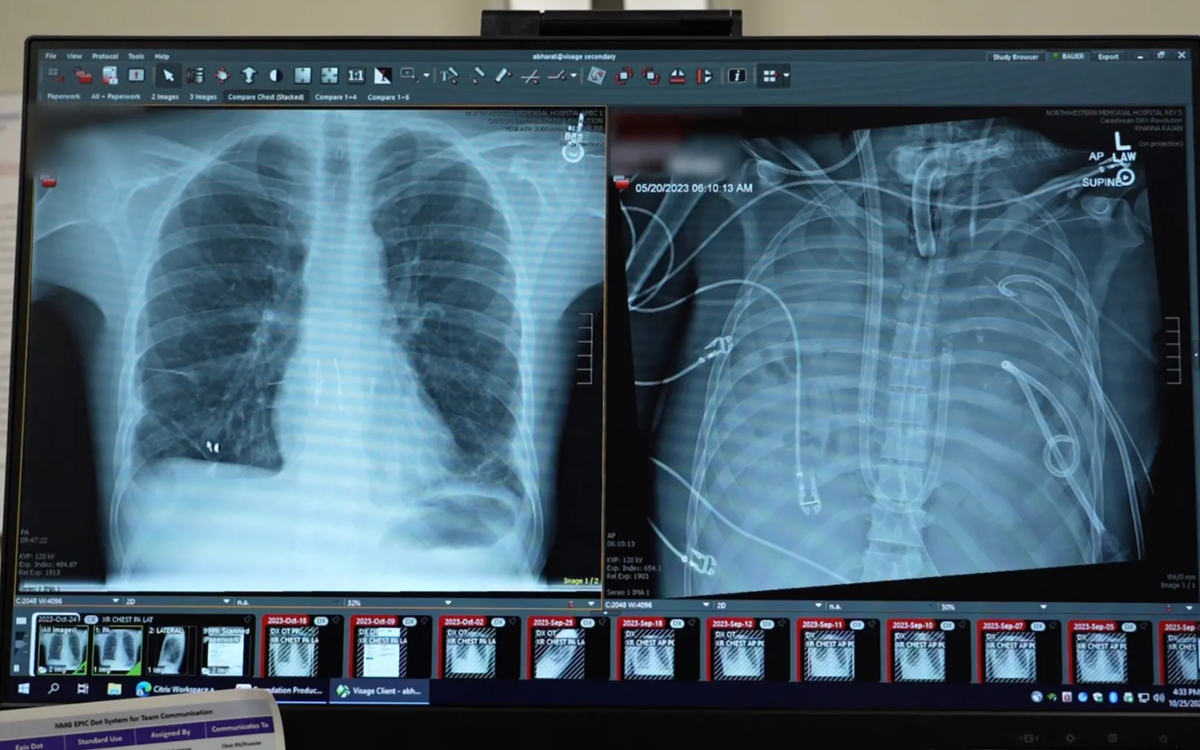

| Kỳ tích y khoa: Sống sót 48 giờ không cần phổi | |

| Trong một báo cáo vừa được công bố trên tạp chí y khoa Med, các bác sĩ tại Mỹ đã cắt bỏ hoàn toàn cả hai lá phổi bị hoại tử của một bệnh nhân 33 tuổi và duy trì sự sống cho anh trong suốt hai ngày....Xem tiếp>>> | |